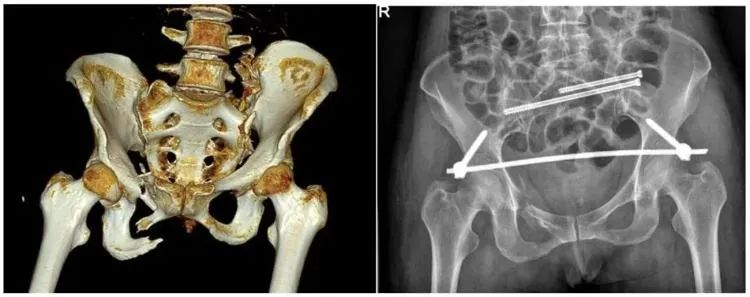

【醫(yī)療科普】:不穩(wěn)定性骨折影像

不穩(wěn)定性骨折

另外,我們根據(jù)骨盆骨折是否穩(wěn)定可以分為穩(wěn)定性的骨折和不穩(wěn)定性的骨折。如果是不穩(wěn)定性的骨折醫(yī)生可能會(huì)建議病人進(jìn)行手術(shù)治療,把不穩(wěn)定性的骨折變成穩(wěn)定性的骨折。